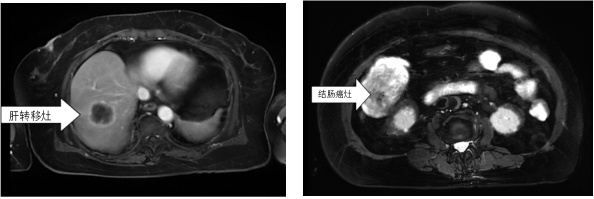

胡竑韡副主任医师经询问病史、查体和CT检查等,判断老人患结肠癌伴肝转移,这一结果让李阿婆一时难以接受,家人也忧心忡忡。

在麻醉科的全力配合下,医护团队配合默契、全力以赴,成功清除了结肠约7cm大肿瘤、肝上约5cm转移病灶,松解了复杂肠粘连。术后,外科联合呼吸科、营养科等,为患者进行抗炎、护肝、化痰、营养支持、对症处理等治疗。患者术后恢复情况良好,顺利出院。